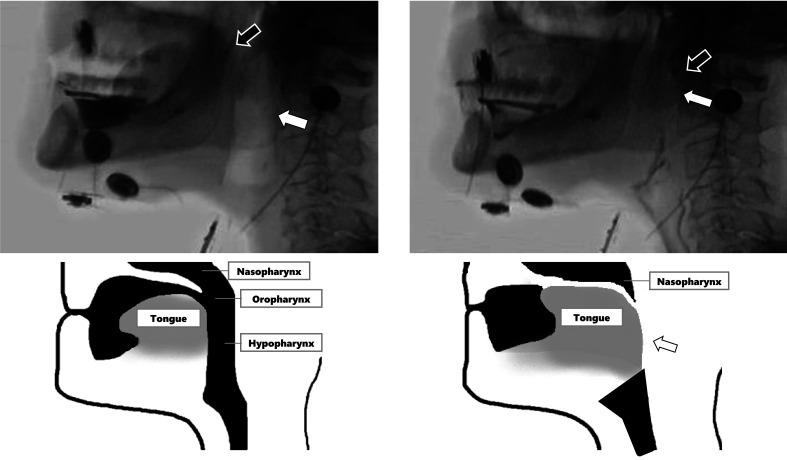

We investigated ERD during volitional swallowing using electroencephalography in three male patients after total laryngectomy for laryngeal cancer (age and time after surgery: Case 1, 75 years, 10 years; Case 2, 85 years, 19 years; Case 3, 73 years, 19 years). In video fluorographic swallowing studies, we observed compensatory tongue movements such as posterior-inferior retraction of the tongue and contact on the posterior pharyngeal wall in all three cases. Significant ERD was localized in the bilateral medial sensorimotor areas and the left lateral parietal area in Case 1, in the bilateral frontal and left temporal areas in Case 2, and in the left prefrontal and premotor areas in Case 3.

我们对3例因喉癌行全喉切除术的男性患者(年龄及术后时间:病例1,75岁,术后10年;病例2,85岁,术后19年;病例3,73岁,术后19年)进行了脑电图检查,以研究自主吞咽过程中的ERD。在电视荧光吞咽造影研究中,我们观察到所有3例患者均有代偿性舌运动,如舌后下退缩及与咽后壁接触。病例1中,显著的ERD定位于双侧内侧感觉运动区和左侧顶叶外侧区;病例2中,定位于双侧额叶和左侧颞叶区;病例3中,定位于左侧前额叶和运动前区。